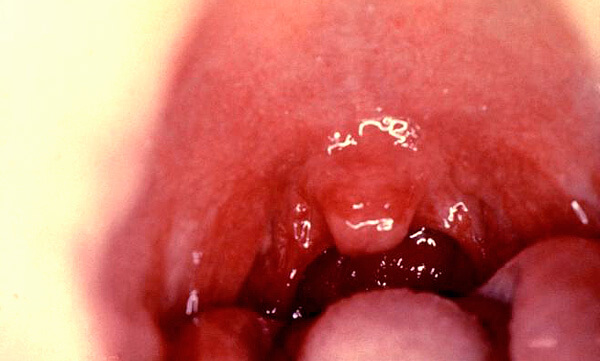

Симптомы катаральной ангины обычно легко узнаваемы: миндалины у пациента сильно воспалены и увеличены, имеют ярко-красный оттенок, воспаление может распространиться на небные дужки. Фотография показывает горло пациента с ангиной, у которого отсутствует повышенная температура:

Также некоторые заболевания могут проявляться без повышения температуры, что иногда приводит к ошибочной диагностике ангины в домашних условиях из-за схожести симптомов:

- Ангина Симановского-Плаута-Венсана (язвенно-пленчатая ангина) — также бактериальное поражение миндалин (чаще одной из них, за что болезнь получила название «односторонняя ангина»), при котором формируются характерные язвы с неприятным поверхностным налетом. Болезнь обычно протекает легко, чаще без повышения температуры и с нормальным общим состоянием больного;

- Грибковый тонзиллит и грибковый фарингит (в народе их называют грибковыми ангинами). При этих заболеваниях либо на миндалинах, либо на задней части горла появляется хорошо заметный сырой белый налет, который больные часто принимают за гной при ангине. В некоторых случаях этот налет, находящийся только на миндалинах, действительно очень похож на настоящие гнойные поражения при стрептококковой инфекции, и провести точную диагностику может только врач на основании культурального исследования отделяемого слизистой оболочки миндалин. На фото — грибковое поражение горла и ротовой полости: Для грибковых заболеваний характерны болевые ощущения в миндалинах, иногда — просто чувство першения в горле, удовлетворительное общее состояние больного и сохранение нормальной температуры тела;